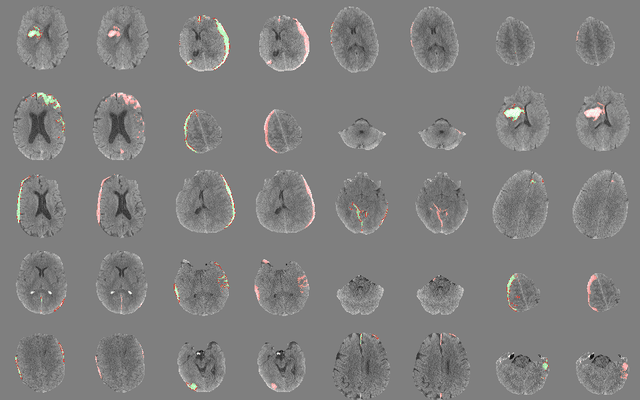

Abstract:Computed tomography (CT) is the imaging modality used in the diagnosis of neurological emergencies, including acute stroke and traumatic brain injury. Advances in deep learning have led to models that can detect and segment hemorrhage on head CT. PatchFCN, one such supervised fully convolutional network (FCN), recently demonstrated expert-level detection of intracranial hemorrhage on in-sample data. However, its potential for similar accuracy outside the training domain is hindered by its need for pixel-labeled data from outside institutions. Also recently, a semi-supervised technique, Noisy Student (NS) learning, demonstrated state-of-the-art performance on ImageNet by moving from a fully-supervised to a semi-supervised learning paradigm. We combine the PatchFCN and Noisy Student approaches, extending semi-supervised learning to an intracranial hemorrhage segmentation task. Surprisingly, the NS model performance surpasses that of a fully-supervised oracle model trained with image-level labels on the same data. It also performs comparably to another recently reported supervised model trained on a labeled dataset 600x larger than that used to train the NS model. To our knowledge, we are the first to demonstrate the effectiveness of semi-supervised learning on a head CT detection and segmentation task.

Abstract:Deep learning for clinical applications is subject to stringent performance requirements, which raises a need for large labeled datasets. However, the enormous cost of labeling medical data makes this challenging. In this paper, we build a cost-sensitive active learning system for the problem of intracranial hemorrhage detection and segmentation on head computed tomography (CT). We show that our ensemble method compares favorably with the state-of-the-art, while running faster and using less memory. Moreover, our experiments are done using a substantially larger dataset than earlier papers on this topic. Since the labeling time could vary tremendously across examples, we model the labeling time and optimize the return on investment. We validate this idea by core-set selection on our large labeled dataset and by growing it with data from the wild.